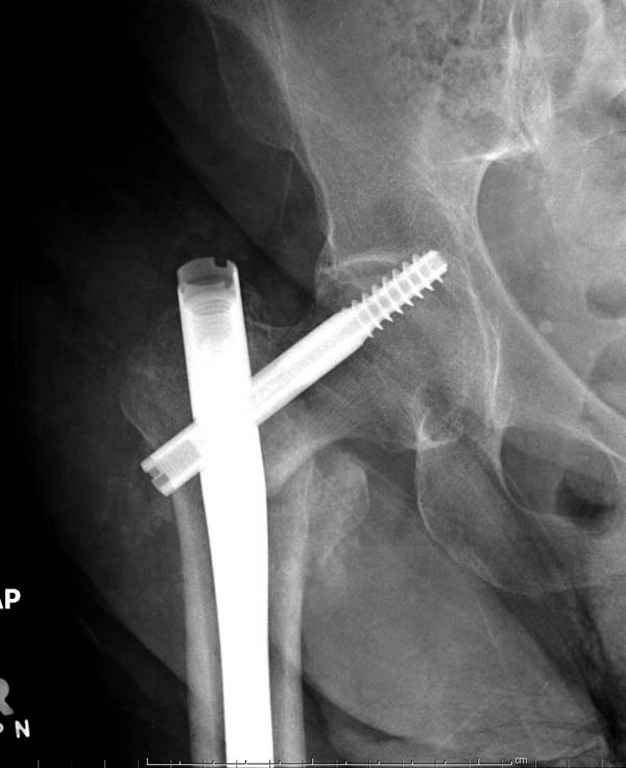

С приходом менее агрессивных блокируемых цефаломедуллярных гвоздей (Gamma 3 и другие) изменилась тактика лечения. Несмотря на то, что вся стабильность держится вокруг одного блокирующего винта, в большинстве случаев гвозди приводили к успеху.

В данном случае в головке бедра и в вертлужной впадине огромный дефект, навряд ли удалением импланта или заменой на другой можно сохранить сустав.

Вашему вниманию представляется похожий случай, пациентке 70, осложнился в течение одного месяца после операции. Ревизия с заменой сустава, кабельная фиксация на трохантер. При установке в дистальном диафизе обнаружен тонкий кортикальный слой и сделана профилактика от возможного перелома аллографтом.